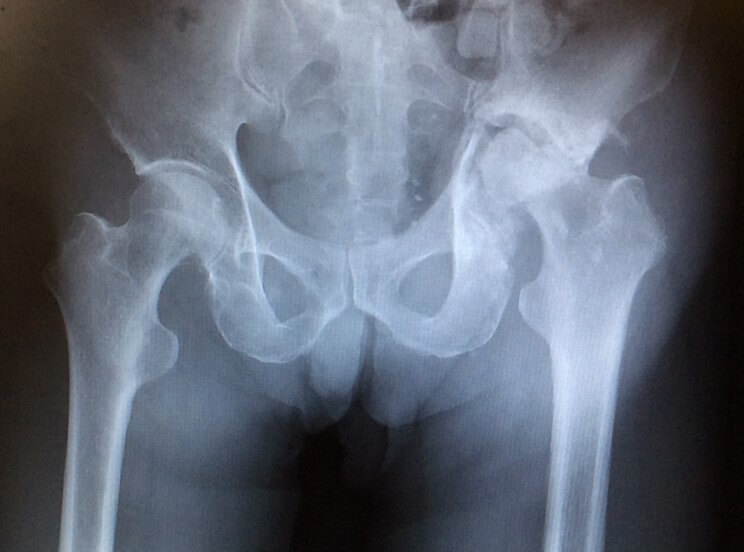

急速破壊型股関節症